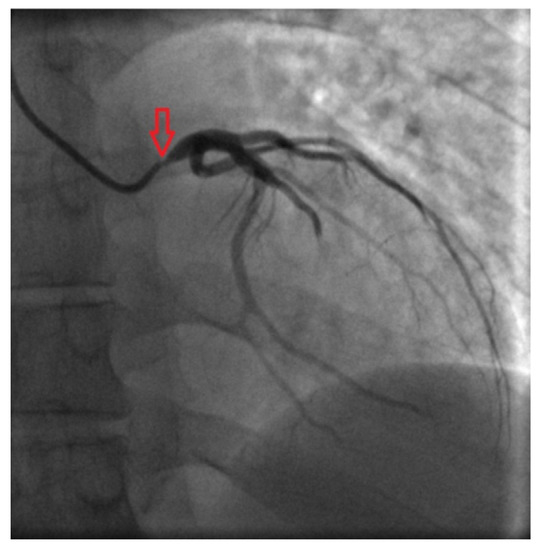

Coronary angiography clarified causes of chest pain: subocclusions of right and left main coronary arteries were found (Fig. 3 and Fig. 4).

Fig. 3. - Left coronary angiogram shows critical left main coronary artery ostial stenosis.